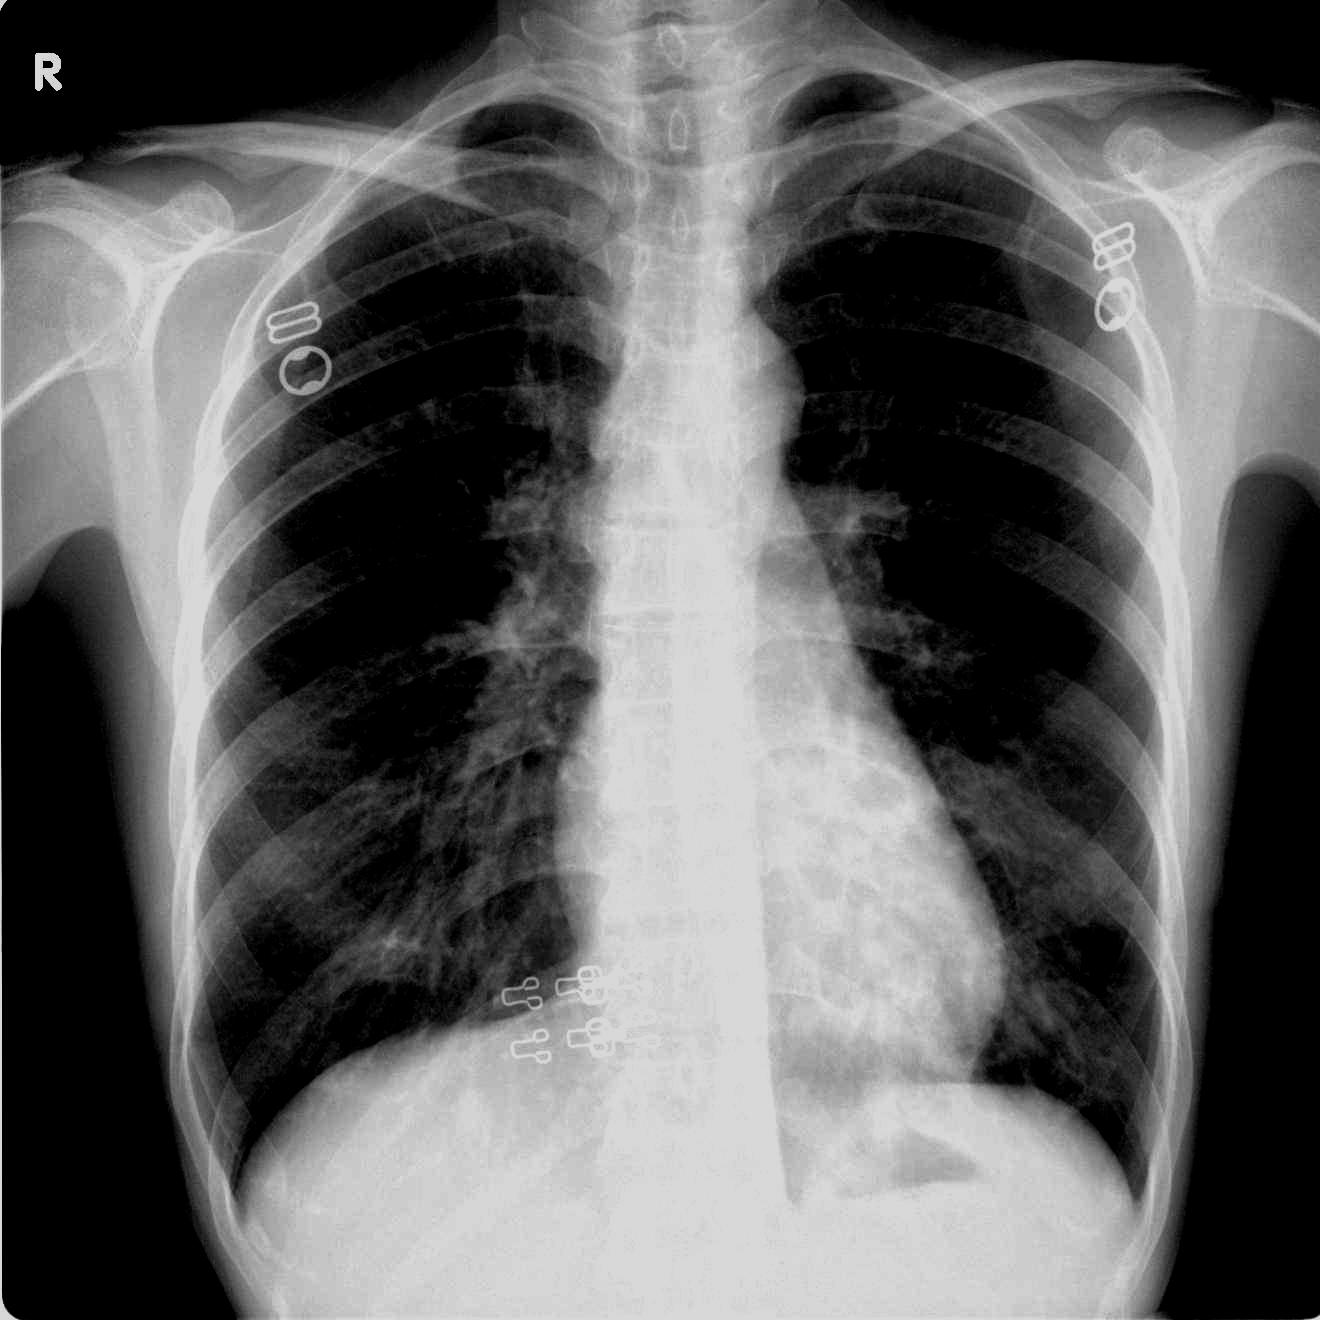

女 40y 咳嗽发热数月。

鉴于有的战友好象没怎么在意观察心影后,又调了一张传上来.

左下肺野内中带示斑片状密度增高影,其内示囊状影,部分囊内似有液平,心影重叠为著,考虑支气管扩张并肺感染。

双肺纹理增多,双下肺纹理呈网格状改变,左心后缘见数个囊状透亮影,结合临床考虑1.肺囊肿合并感染,2.支扩合并感染(患者没有咳血丝痰),建议ct扫描

左下肺(心影后)可见多个囊状影,壁稍后,部分囊内可见液平,考虑:左下肺支扩伴感染

双侧肺纹理增强,左下肺野见斑片状增密不均影,以心后区为明显。结合病史--女 40y 咳嗽发热数月。考虑支扩肺部感染。建议结合临床及ct检查

考虑左下肺支扩并感染(肺隔离症有待排除),可行ct进一步检查。

左下肺心影后纹理增粗,紊乱呈蜂窝状,边缘模糊,支气管扩张并感染不除外.